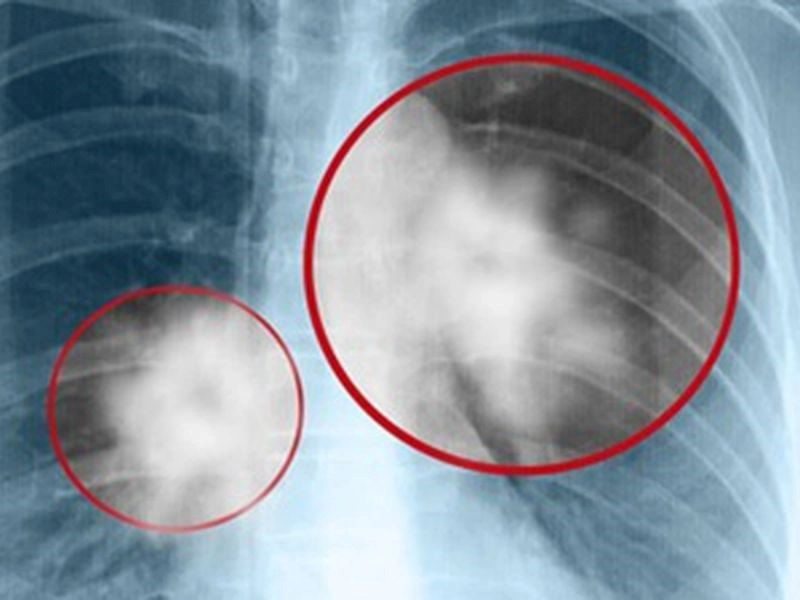

Ung thư phổi di căn xương ở giai đoạn 4

Ung thư phổi di căn xương thường xảy ra ở giai đoạn cuối, đặc biệt là giai đoạn 4. Trong giai đoạn này, bệnh nhân có thể gặp phải các triệu chứng rõ rệt như đau xương, mỏi cơ, và yếu chân. Di căn xương là hiện tượng các tế bào ung thư từ khối u phổi di chuyển đến các mô xương qua máu hoặc hệ bạch huyết.

Xương là một trong ba vị trí di căn phổ biến nhất của ung thư phổi, chỉ đứng sau gan và tuyến thượng thận, với khoảng 30%-40% bệnh nhân ung thư phổi giai đoạn cuối bị ảnh hưởng. Các nghiên cứu cho thấy ung thư phổi di căn xương thường ảnh hưởng đến những khu vực như cột sống, xương sườn, xương chậu, xương đùi, xương cánh tay trên, xương bả vai và xương ức. Ngoài ra, bệnh cũng có thể lan đến các xương ở bàn tay và bàn chân, gây đau đớn và hạn chế khả năng vận động của bệnh nhân.